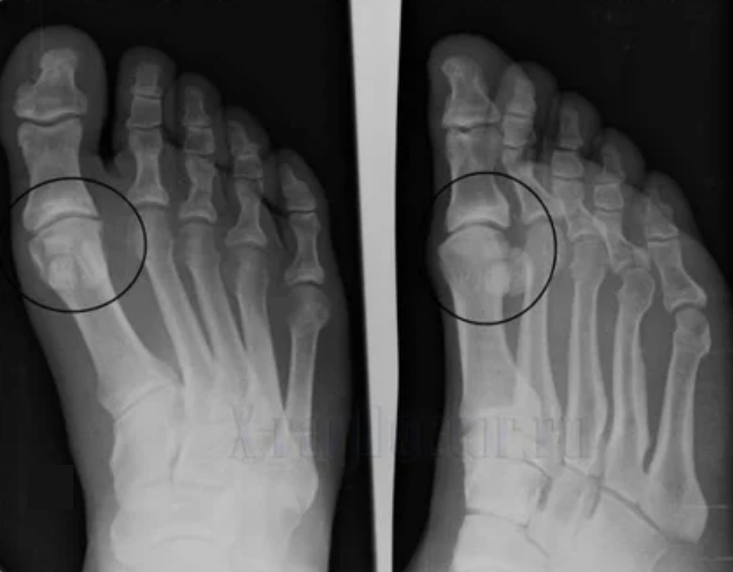

Diagnostikoa egiteko, erreumatologoek gaixoaren kexak aztertzen dituzte eta X -Ray azterketa bat preskribatu. Gehienetan erradiografia 2 proiekzioetan erabiltzen da. Medikuak nahaste disstrofikoen presentzia du Hyaline kartilagoan eta hezur-junturetan. Artikuluaren hutsunea murrizten bada, hezurrak deformatu edo berdindu egiten dira, kartilagoaren gainazalean dauden formazio kistikoak daude, artrosikoen seinale nabarmenak dira. Ikuskapenean, Artrosia artikulazioaren ezegonkortasuna adierazten du: gorputz-adarren ardatza eta subluxazioa asaldatuta dago.

Sarritan x -Ray argazki bat ezin da artikulazioaren egoerari buruzko informazio osoa eman. Azterketa sakonagoa lortzeko, konputatutako tomografia aginduta dago, hezurrak aztertzeko eraginkorra da. MRI maiz erabiltzen da ehun bigunak ikasteko.